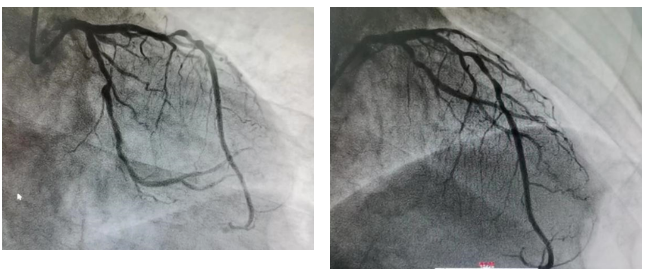

造影结果

LM:远段狭窄80%。

LAD:斑块浸润,开口及近段弥漫狭窄70-95%。

LCX:开口约狭窄70%,高位OM开口狭窄90%。

RCA:斑块浸润,远端狭窄50%。

▲ 最后造影结果理想满意